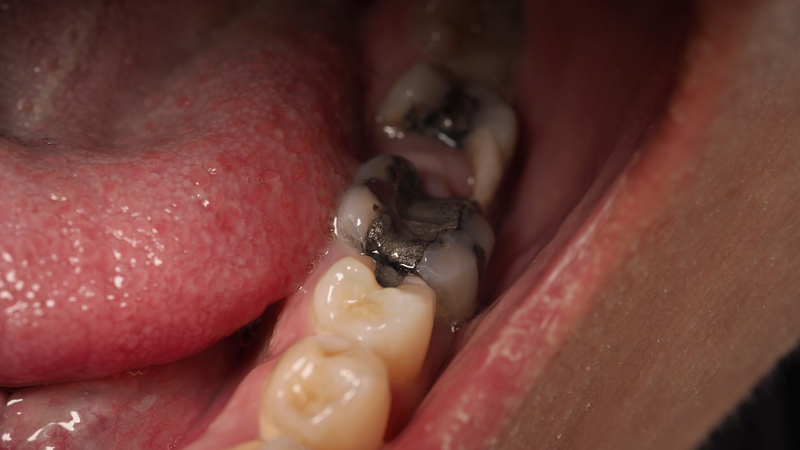

Sâu răng ở vị trí răng khôn thường không gây đau ngay mà tiến triển âm thầm. Chỉ khi vết sâu chạm đến tủy, cơn đau mới trở nên rõ rệt và khó chịu.

Răng khôn thường bị sâu do khó vệ sinh, và vi khuẩn từ răng khôn có thể lan sang mặt tiếp giáp của răng số 7. Điều này khiến cả hai răng đều gặp nguy cơ tổn thương nghiêm trọng.

Nhổ bỏ là lựa chọn thường được bác sĩ cân nhắc khi nguy cơ biến chứng cao. Quan trọng là phải xác định rõ hướng mọc và tình trạng mô quanh răng trước khi thực hiện.